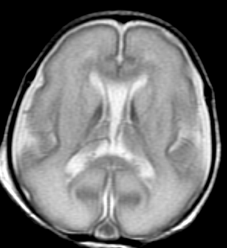

Blüml and colleagues have been studying preterm infants to learn more about how premature birth might cause changes in brain structure that may be associated with clinical problems observed later in life. Much of the focus has been on the brain's white matter, which transmits signals and enables communication between different parts of the brain. While some white matter damage is readily apparent on structural magnetic resonance imaging (MRI), Blüml's group has been using magnetic resonance spectroscopy (MRS) to look at differences on a microscopic level.

In this study, the researchers compared the concentrations of certain chemicals associated with mature white matter and gray matter in 51 full-term and 30 preterm infants. The study group had normal structural MRI findings, but MRS results showed significant differences in the biochemical maturation of white matter between the term and preterm infants, suggesting a disruption in the timing and synchronization of white and gray matter maturation. Gray matter is the part of the brain that processes and sends out signals.